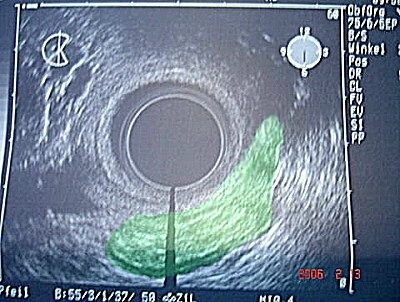

Abb. 3 bis 5: Durch die endo-vaginale Ultraschalluntersuchung ließ sich ein bösartiger Tumor - hier grün hinterlegt - darstellen, der sich ausschließlich auf die Scheidenhinterwand beschränkt hat. Abb. 3 bis 5: Durch die endo-vaginale Ultraschalluntersuchung ließ sich ein bösartiger Tumor - hier grün hinterlegt - darstellen, der sich ausschließlich auf die Scheidenhinterwand beschränkt hat.